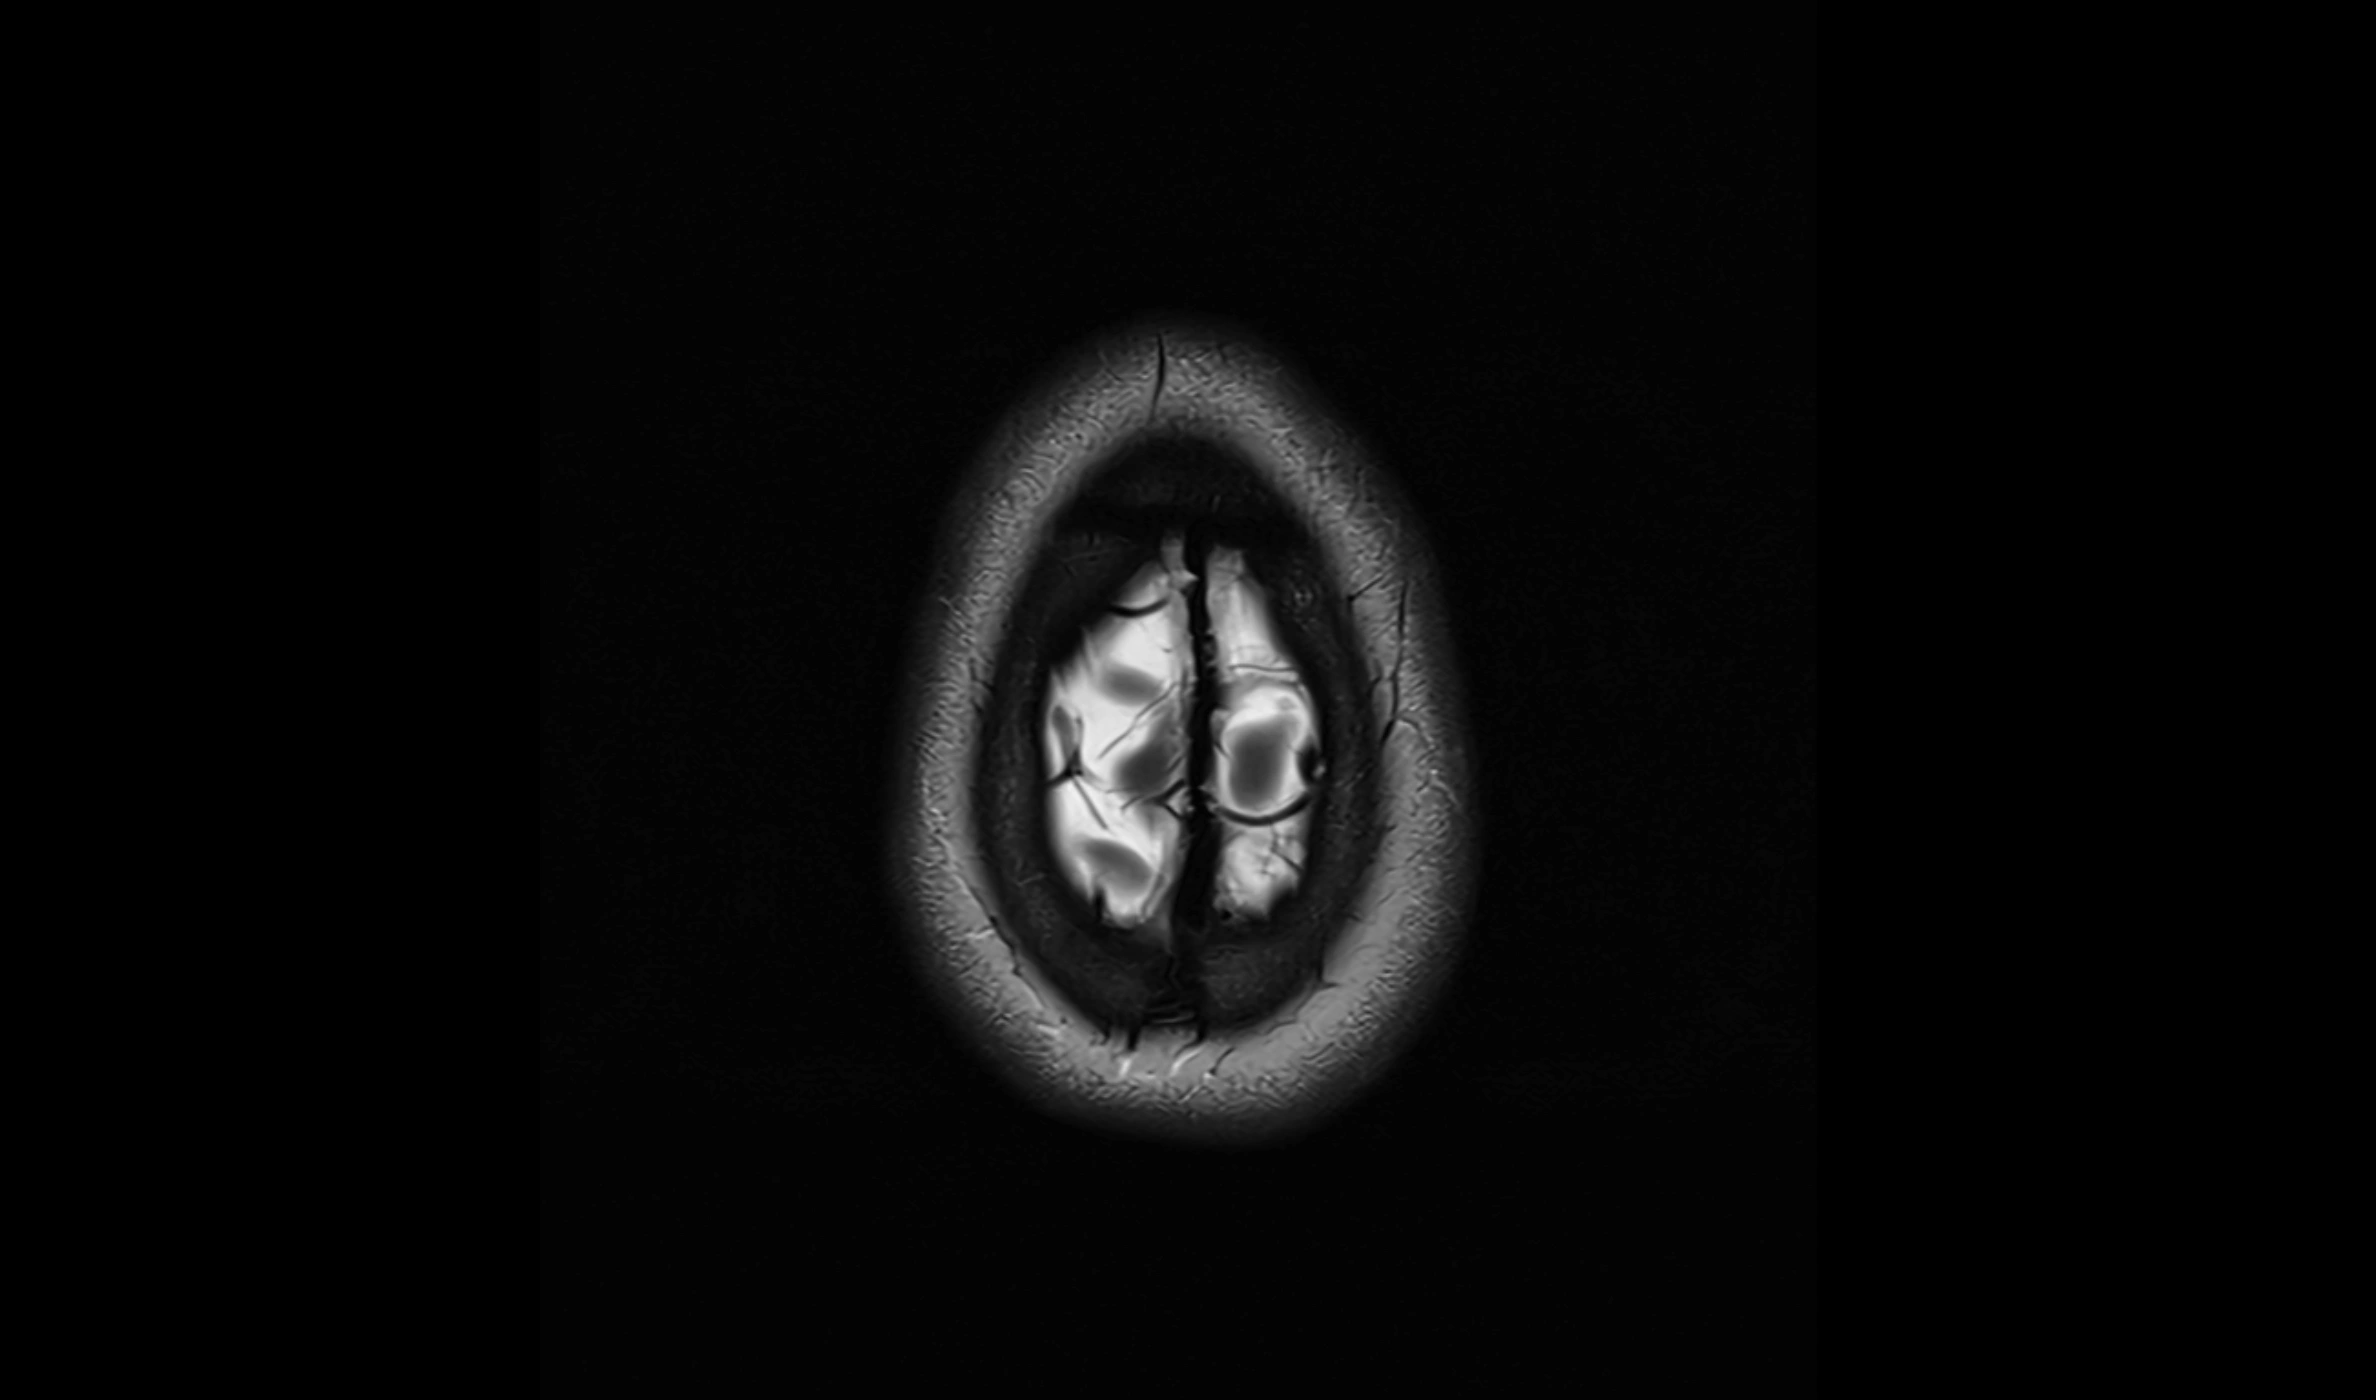

MRI images

image